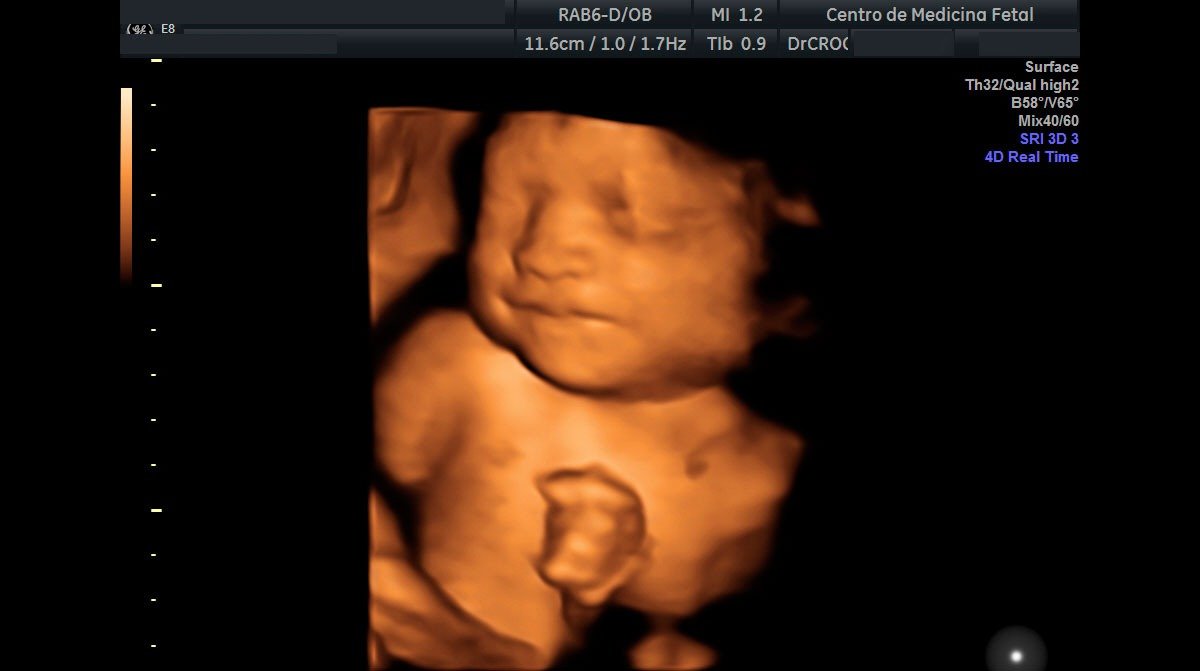

Centro de Medicina Fetal

CENMEF es un centro dedicado al diagnóstico y tratamiento de patologías prenatales. Somos el primer centro privado en nuestro país que ofrece atención especializada por médicos gineco-obstetras CERTIFICADOS INTERNACIONALMENTE por la Fundación de Medicina Fetal de Londres – Inglaterra